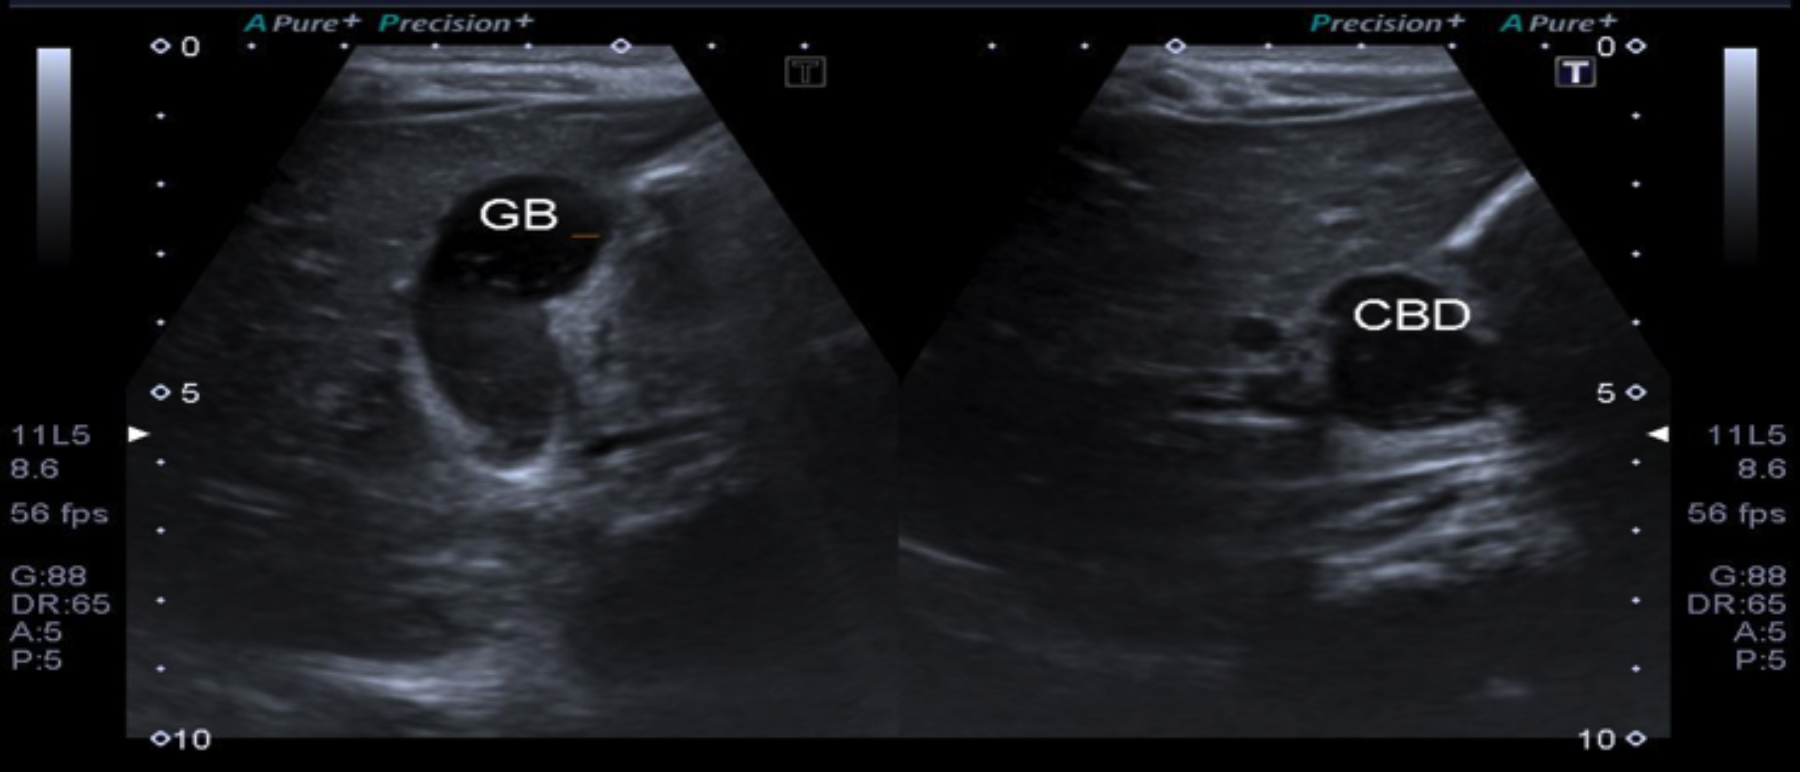

An abdominal ultrasound was performed, revealing fusiform dilatation of the common bile duct (CBD), suggestive of a Type I choledochal cyst (according to the Todani classification), with minimal sludge and micro-calculi in the distal CBD (choledocholithiasis). The gallbladder was moderately distended and filled with sludge and micro-calculi.

Figure  1:  Moderately distended gallbladder with sludge and micro- calculi and dilatation of proximal common bile duct with internal micro- calculi suggesting Type I choledochal cyst with choledocholithiasis.